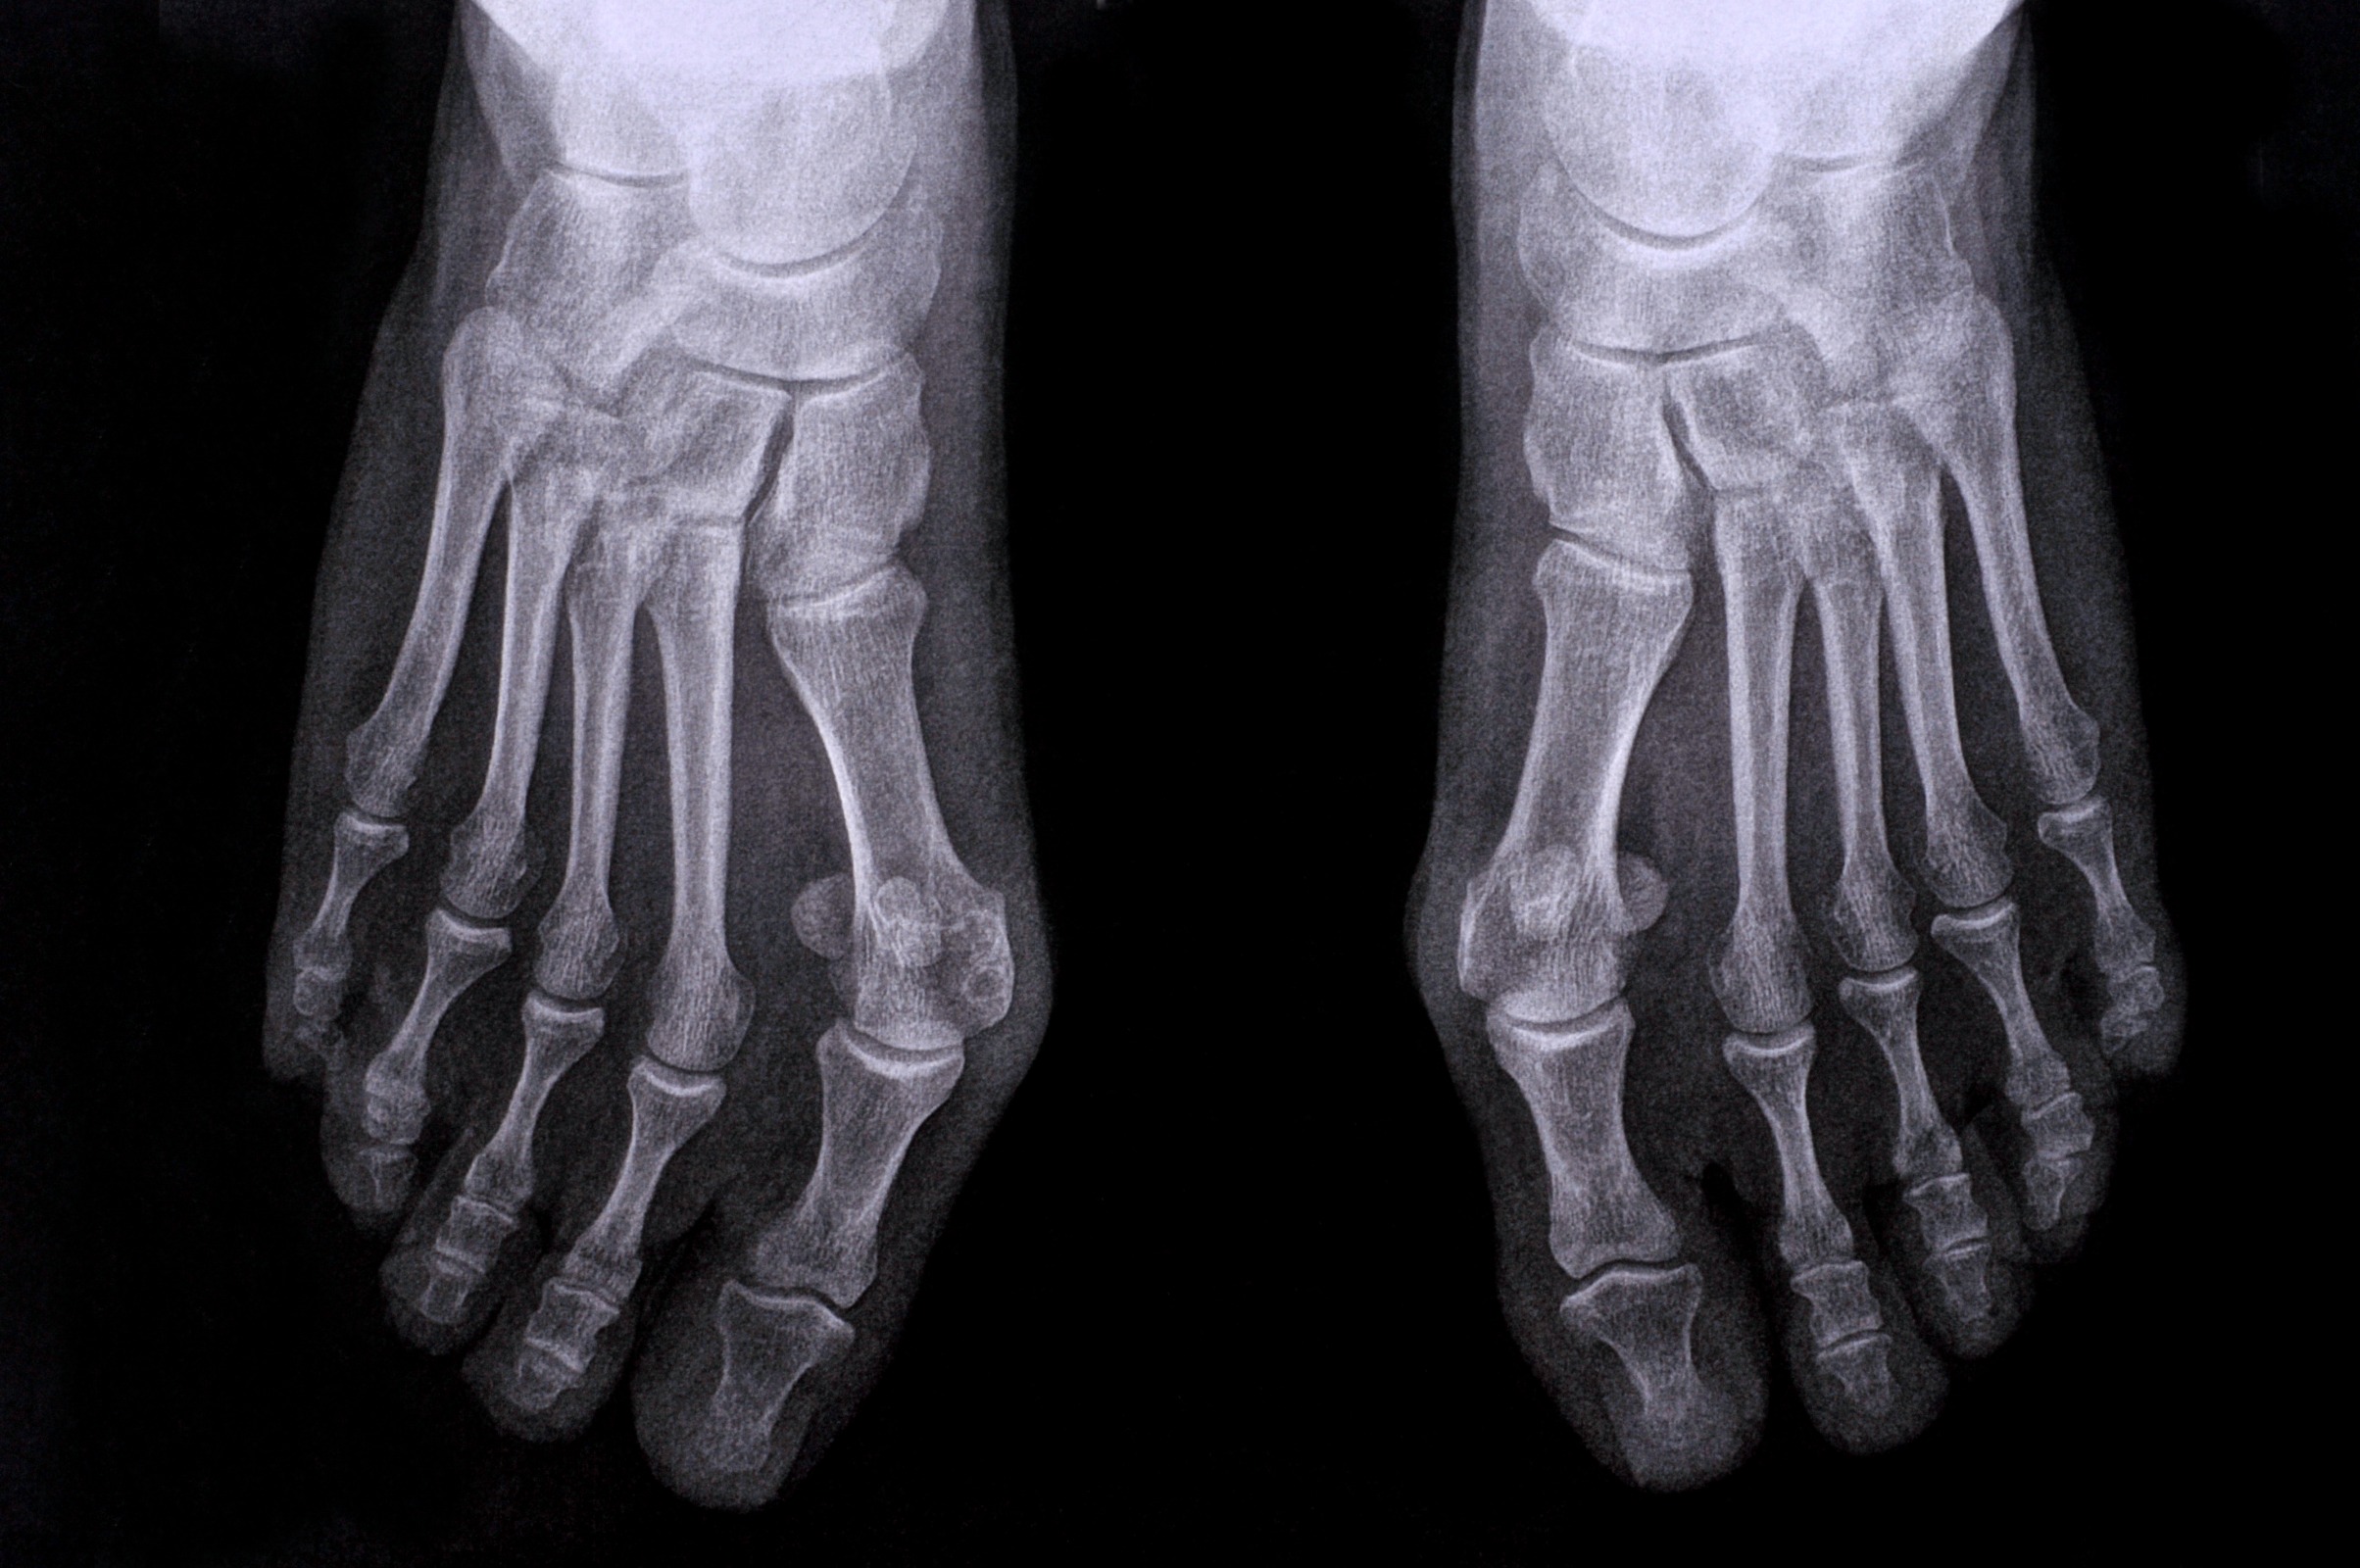

Ever wondered what that bony lump on the side of your foot is? Chances are it's a Bunion. Bunions are relatively harmless and thankfully do not usually require any medical intervention. However, when left to their own devices, they can cause heaps of pain and discomfort, drastically impacting your quality of life.